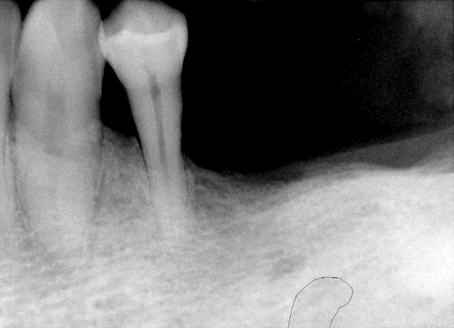

Fig.3 When the pan in Fig.2 was taken, the

patient requested more implants in the lower left quadrant. To

reduce thread exposure, we planned to place 2 implants (8 mm long) (#19 (pink tracing

line) and 20 (yellow) on the either side of the mental nerve and below the

ridge. These 2 implants should be above the inferior alveolar nerve

and incisive nerve, respectively. #20 implant should avoid touching

the neighboring root. An alternative was proposed to extract #21,

place implants at #19 and 21, and fabricate 3-unit fixed prosthetic

denture. The patient declined.

Notice the angulation of the implant for #20. |